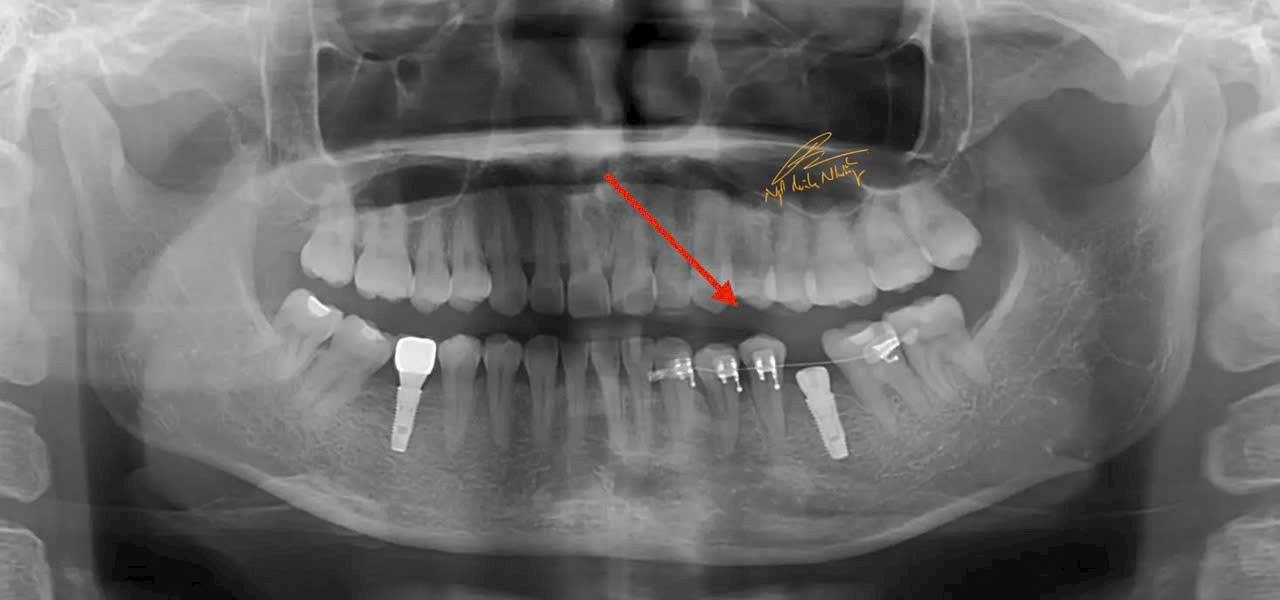

Teo xương hàm : Khi mất răng, xương hàm không còn được kích thích bởi các lực nhai, dẫn đến việc mất dần chất lượng và khối lượng xương tại khu vực mất răng. Điều này có thể làm thay đổi khuôn mặt và làm giảm khả năng lắp răng giả hoặc cấy ghép sau này.

Di chuyển các răng còn lại : Khi mất răng, các răng còn lại có thể bị xô lệch, làm thay đổi cấu trúc của hàm và gây ra các vấn đề về khớp cắn.

Cấy ghép răng (Implant) : Đây là phương pháp phổ biến và hiệu quả nhất để phục hồi răng đã mất. Cấy ghép răng giúp phục hồi chức năng nhai và ngăn ngừa tình trạng teo xương hàm. Cấy ghép được cấy vào xương hàm và có thể lắp răng giả lên đó.